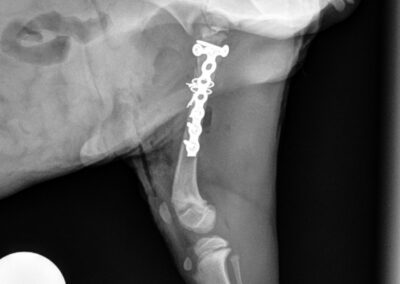

Tibial Plateau Leveling Osteotomy (TPLO)

TPLO is a surgical technique that stabilizes the knee by altering the biomechanics of the joint. By changing the angle of the tibial plateau, the procedure eliminates the need for the cranial cruciate ligament during weight bearing, helping to improve comfort and function during movement.